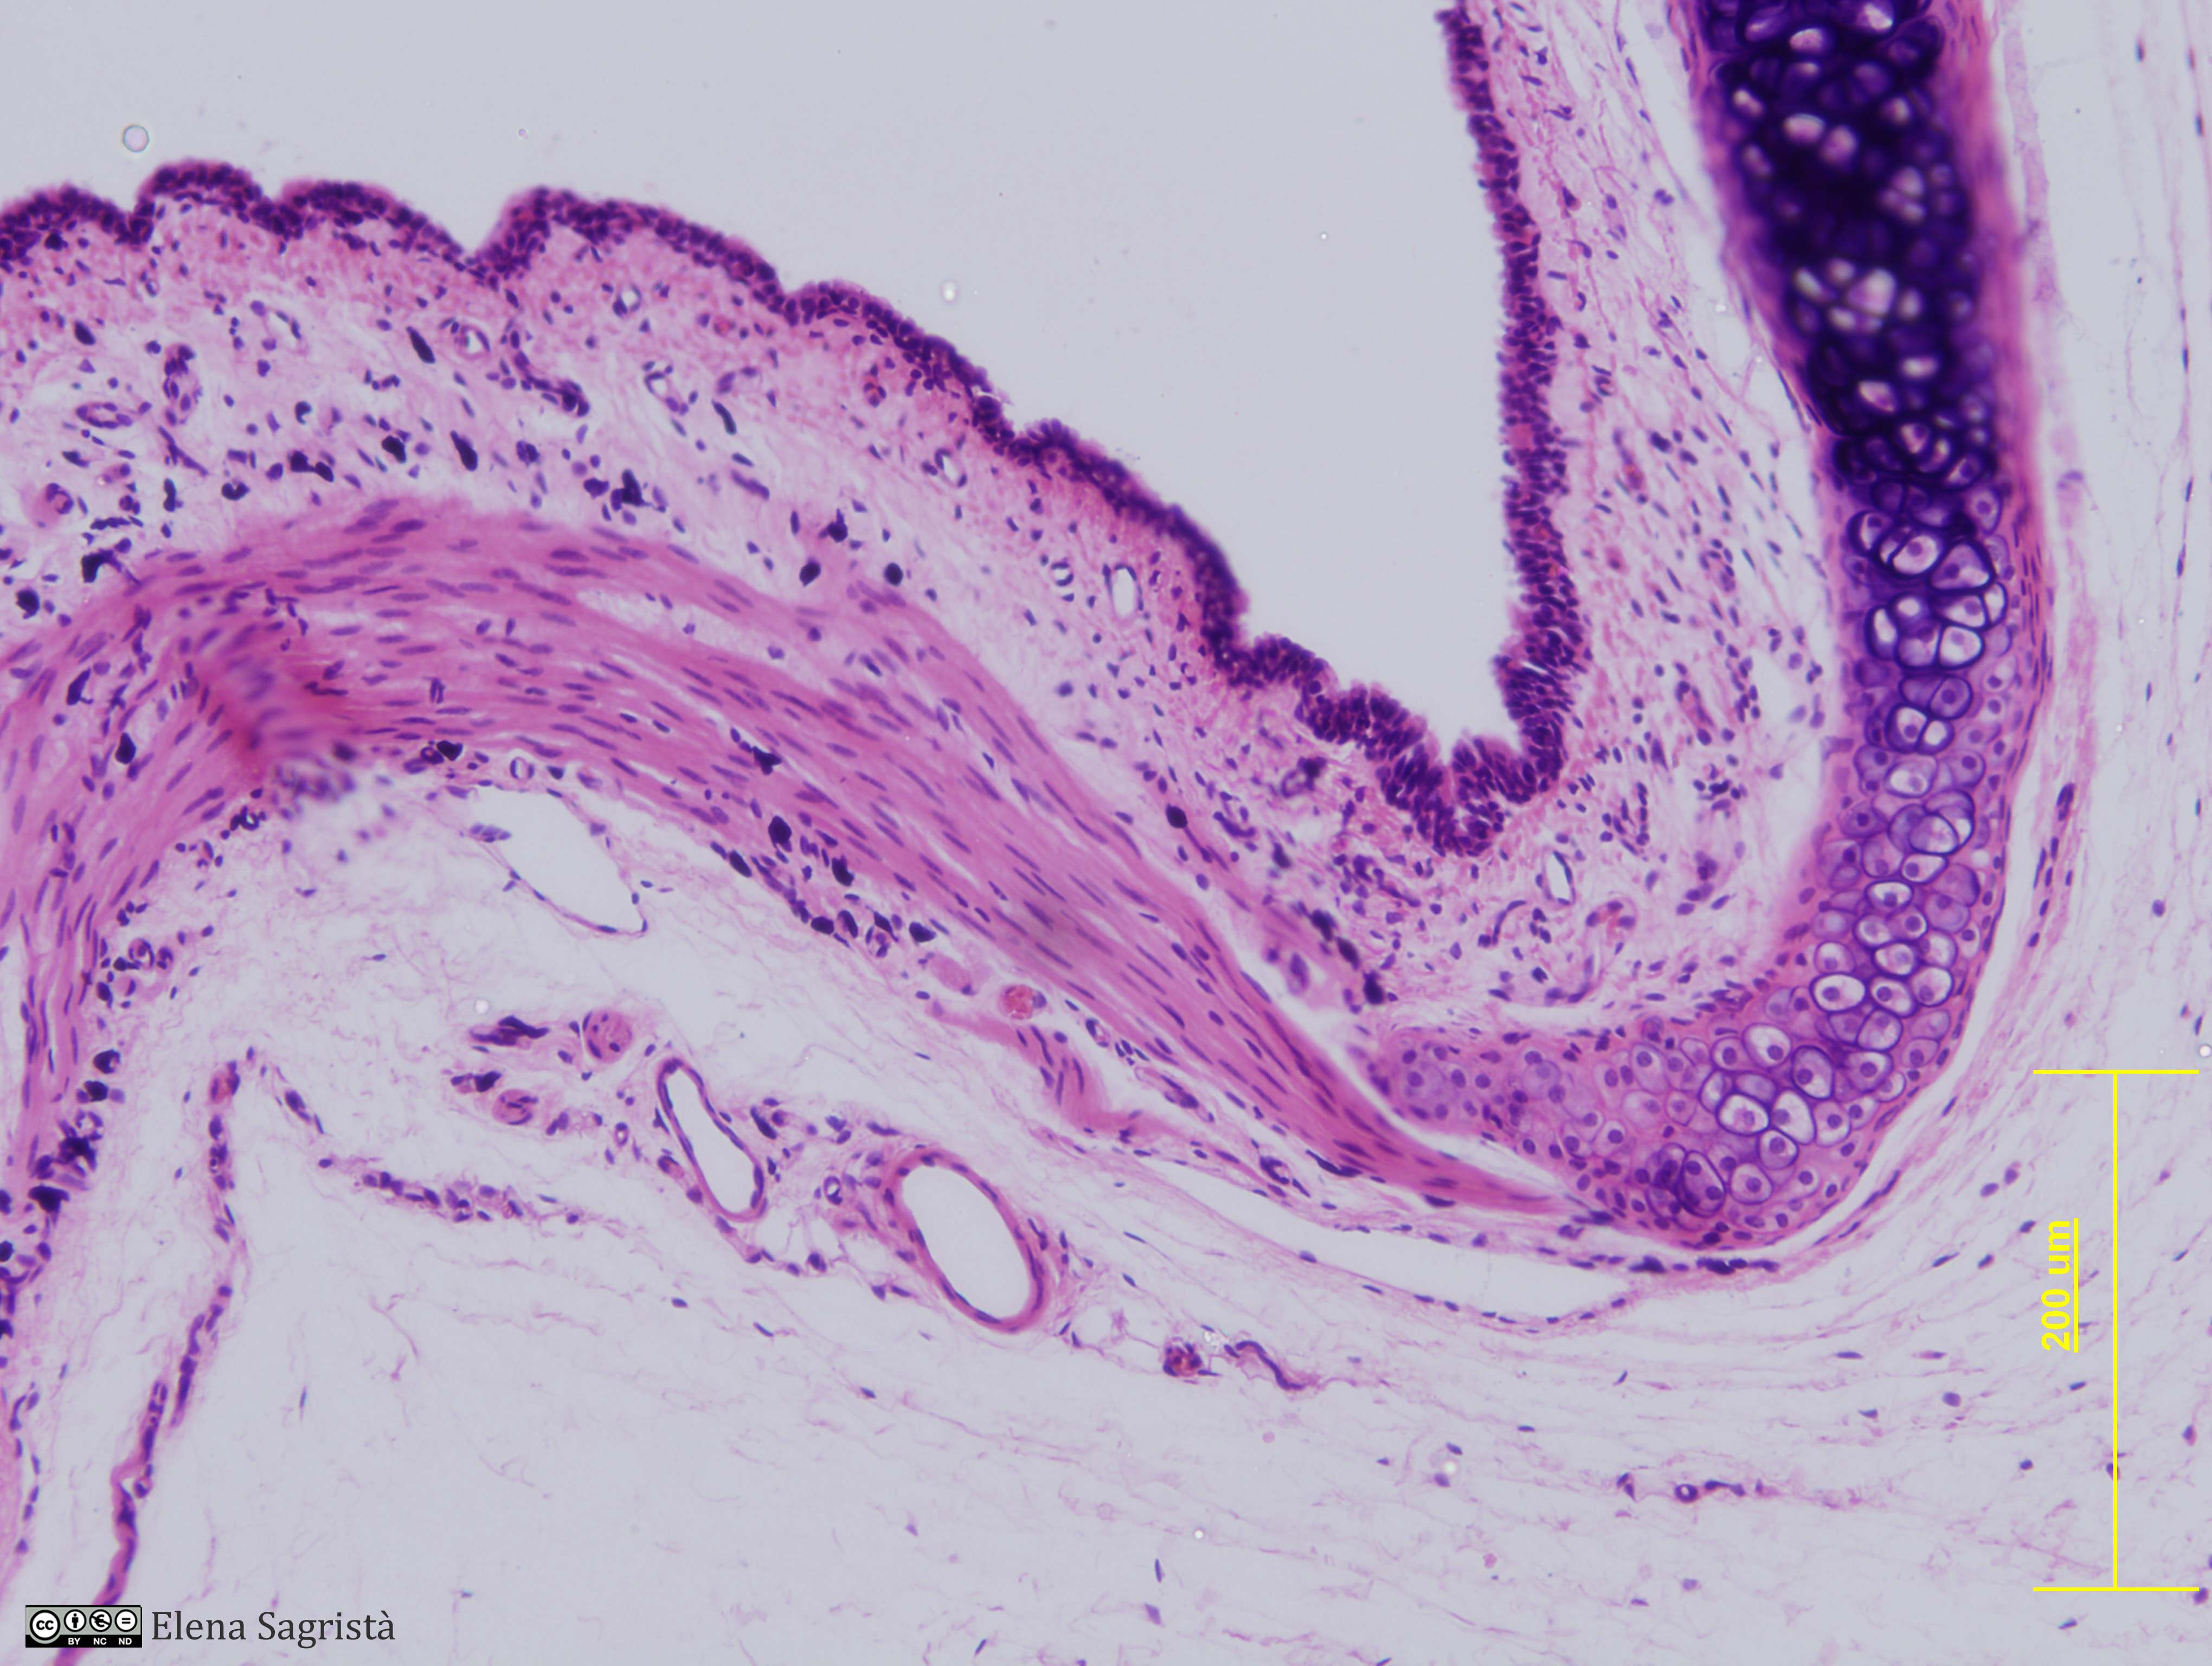

Histologia imatges: 12 Tràquea

Imatges de preparacions histològiques de Tràquea. Microscopia òptica.